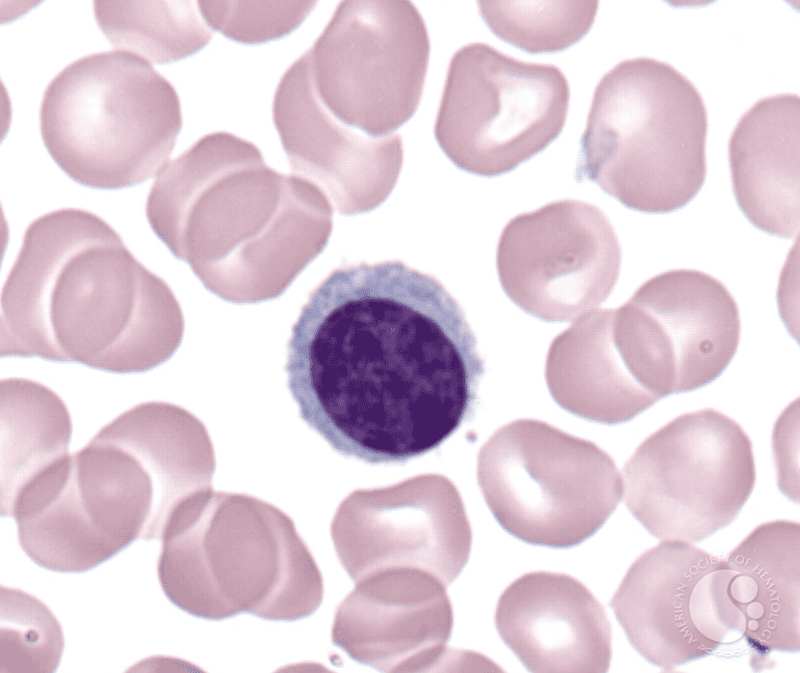

Neutrophil

Lymphocyte

[Function of a] Lymphocyte

Mount immune response by direct cell attack of via antibody production

[Definition of] Leukocytosis

Increase in the number of white blood cells in blood, especially during infection

[Definition of] Leucopenia

Reduction in the number of white blood cells in blood, typical of various diseases

[Definition of] Leukemia

Uncontrolled growth of immature, abnormal (non-functional) leukocytes

Order of Leukocytes from most numerous to least numerous

Neutrophil --> Lymphocyte --> Monocyte --> Eosinophil --> Basophil

(Never Let Monkeys Eat Bananas)